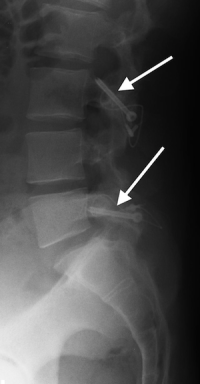

(Click to Enlarge Image) Lateral X-ray of pars interarticularis fractures of L3 and L5 in a 15year old boy who has fail. Black arrow points tominimal slip of L5 on S1. The MRI notes a normal disc at that level.